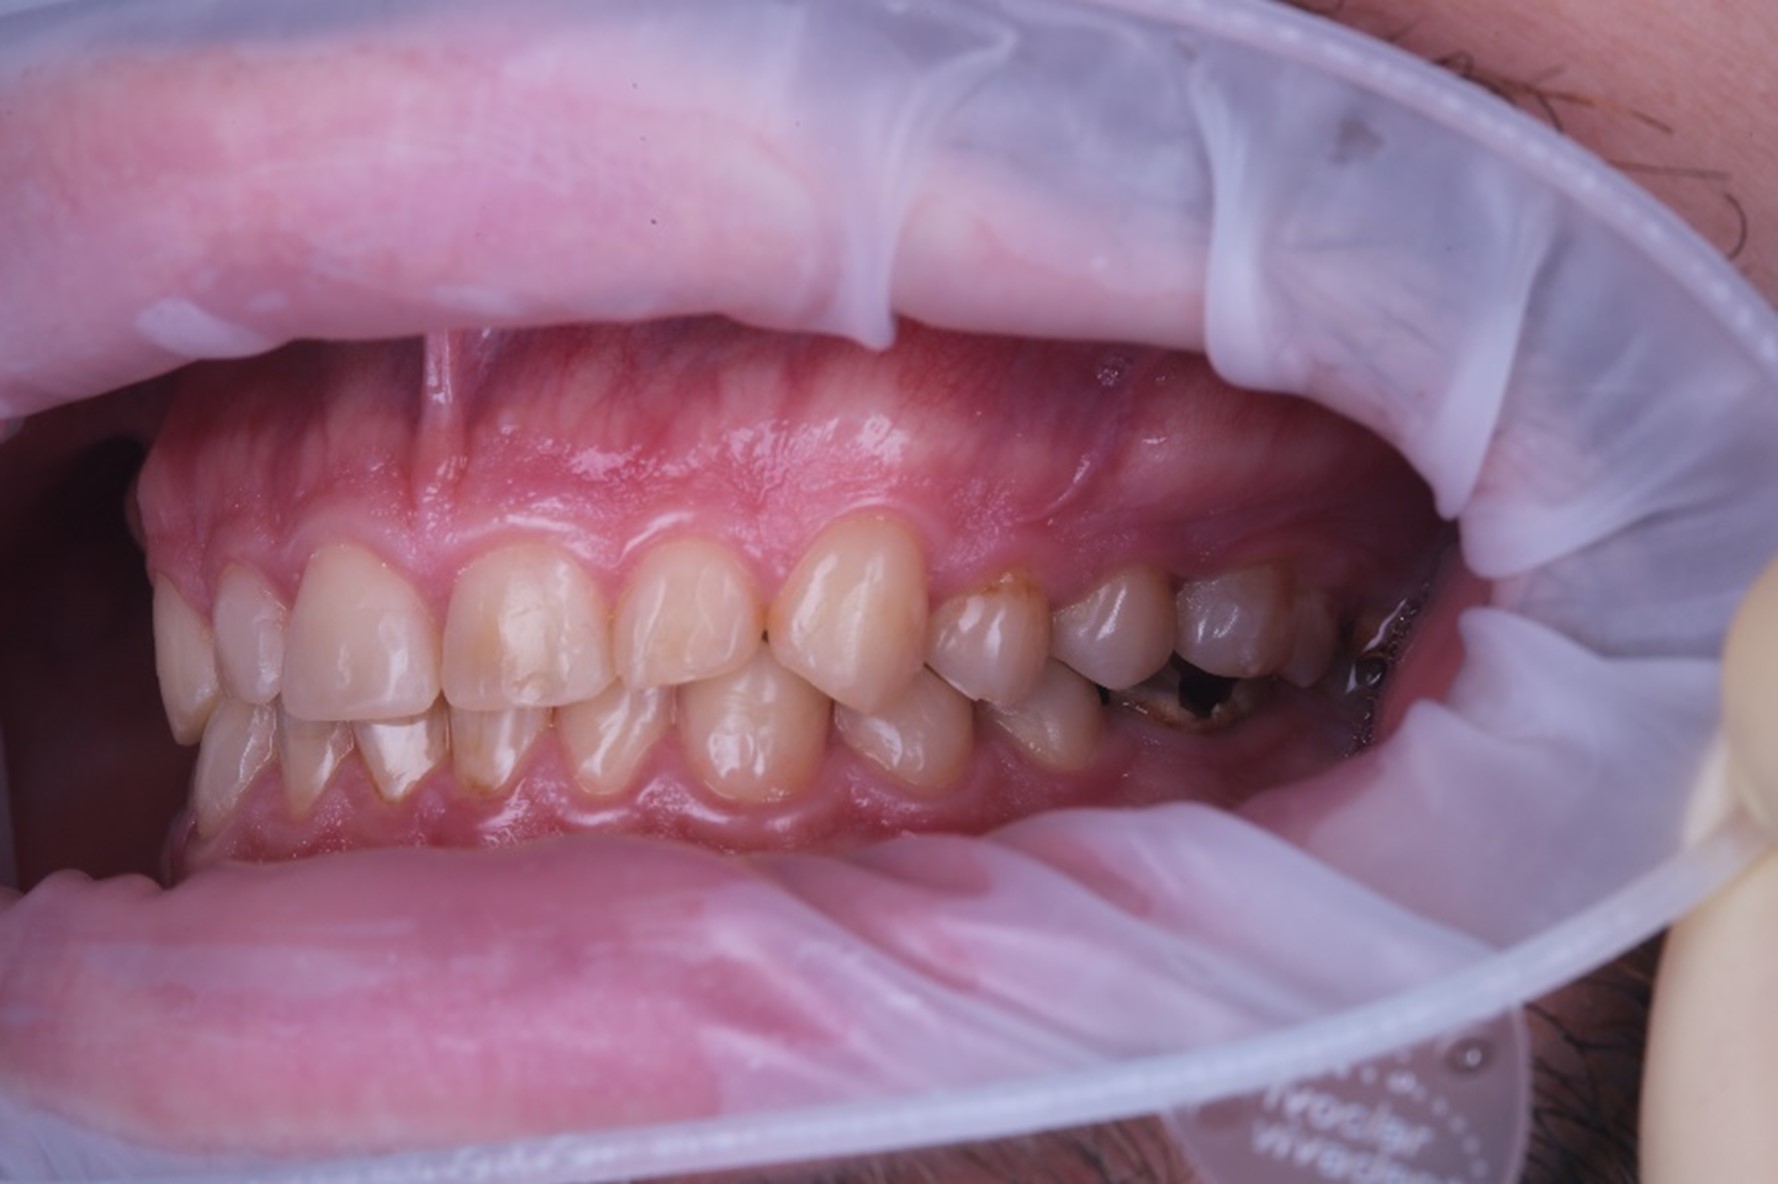

После лечения у терапевта зубы выглядели уже вот так

Но Ваня — кремень: вернулся.

Затем хирург удалил ему зубы на нижней и верхней челюстях. Я снова подумал, что пациент может на этом остановиться, не дожидаясь, когда мы закроем керамической реставрацией разрушенные зубы. Но он дождался, пока приживутся импланты, и продолжил лечение.